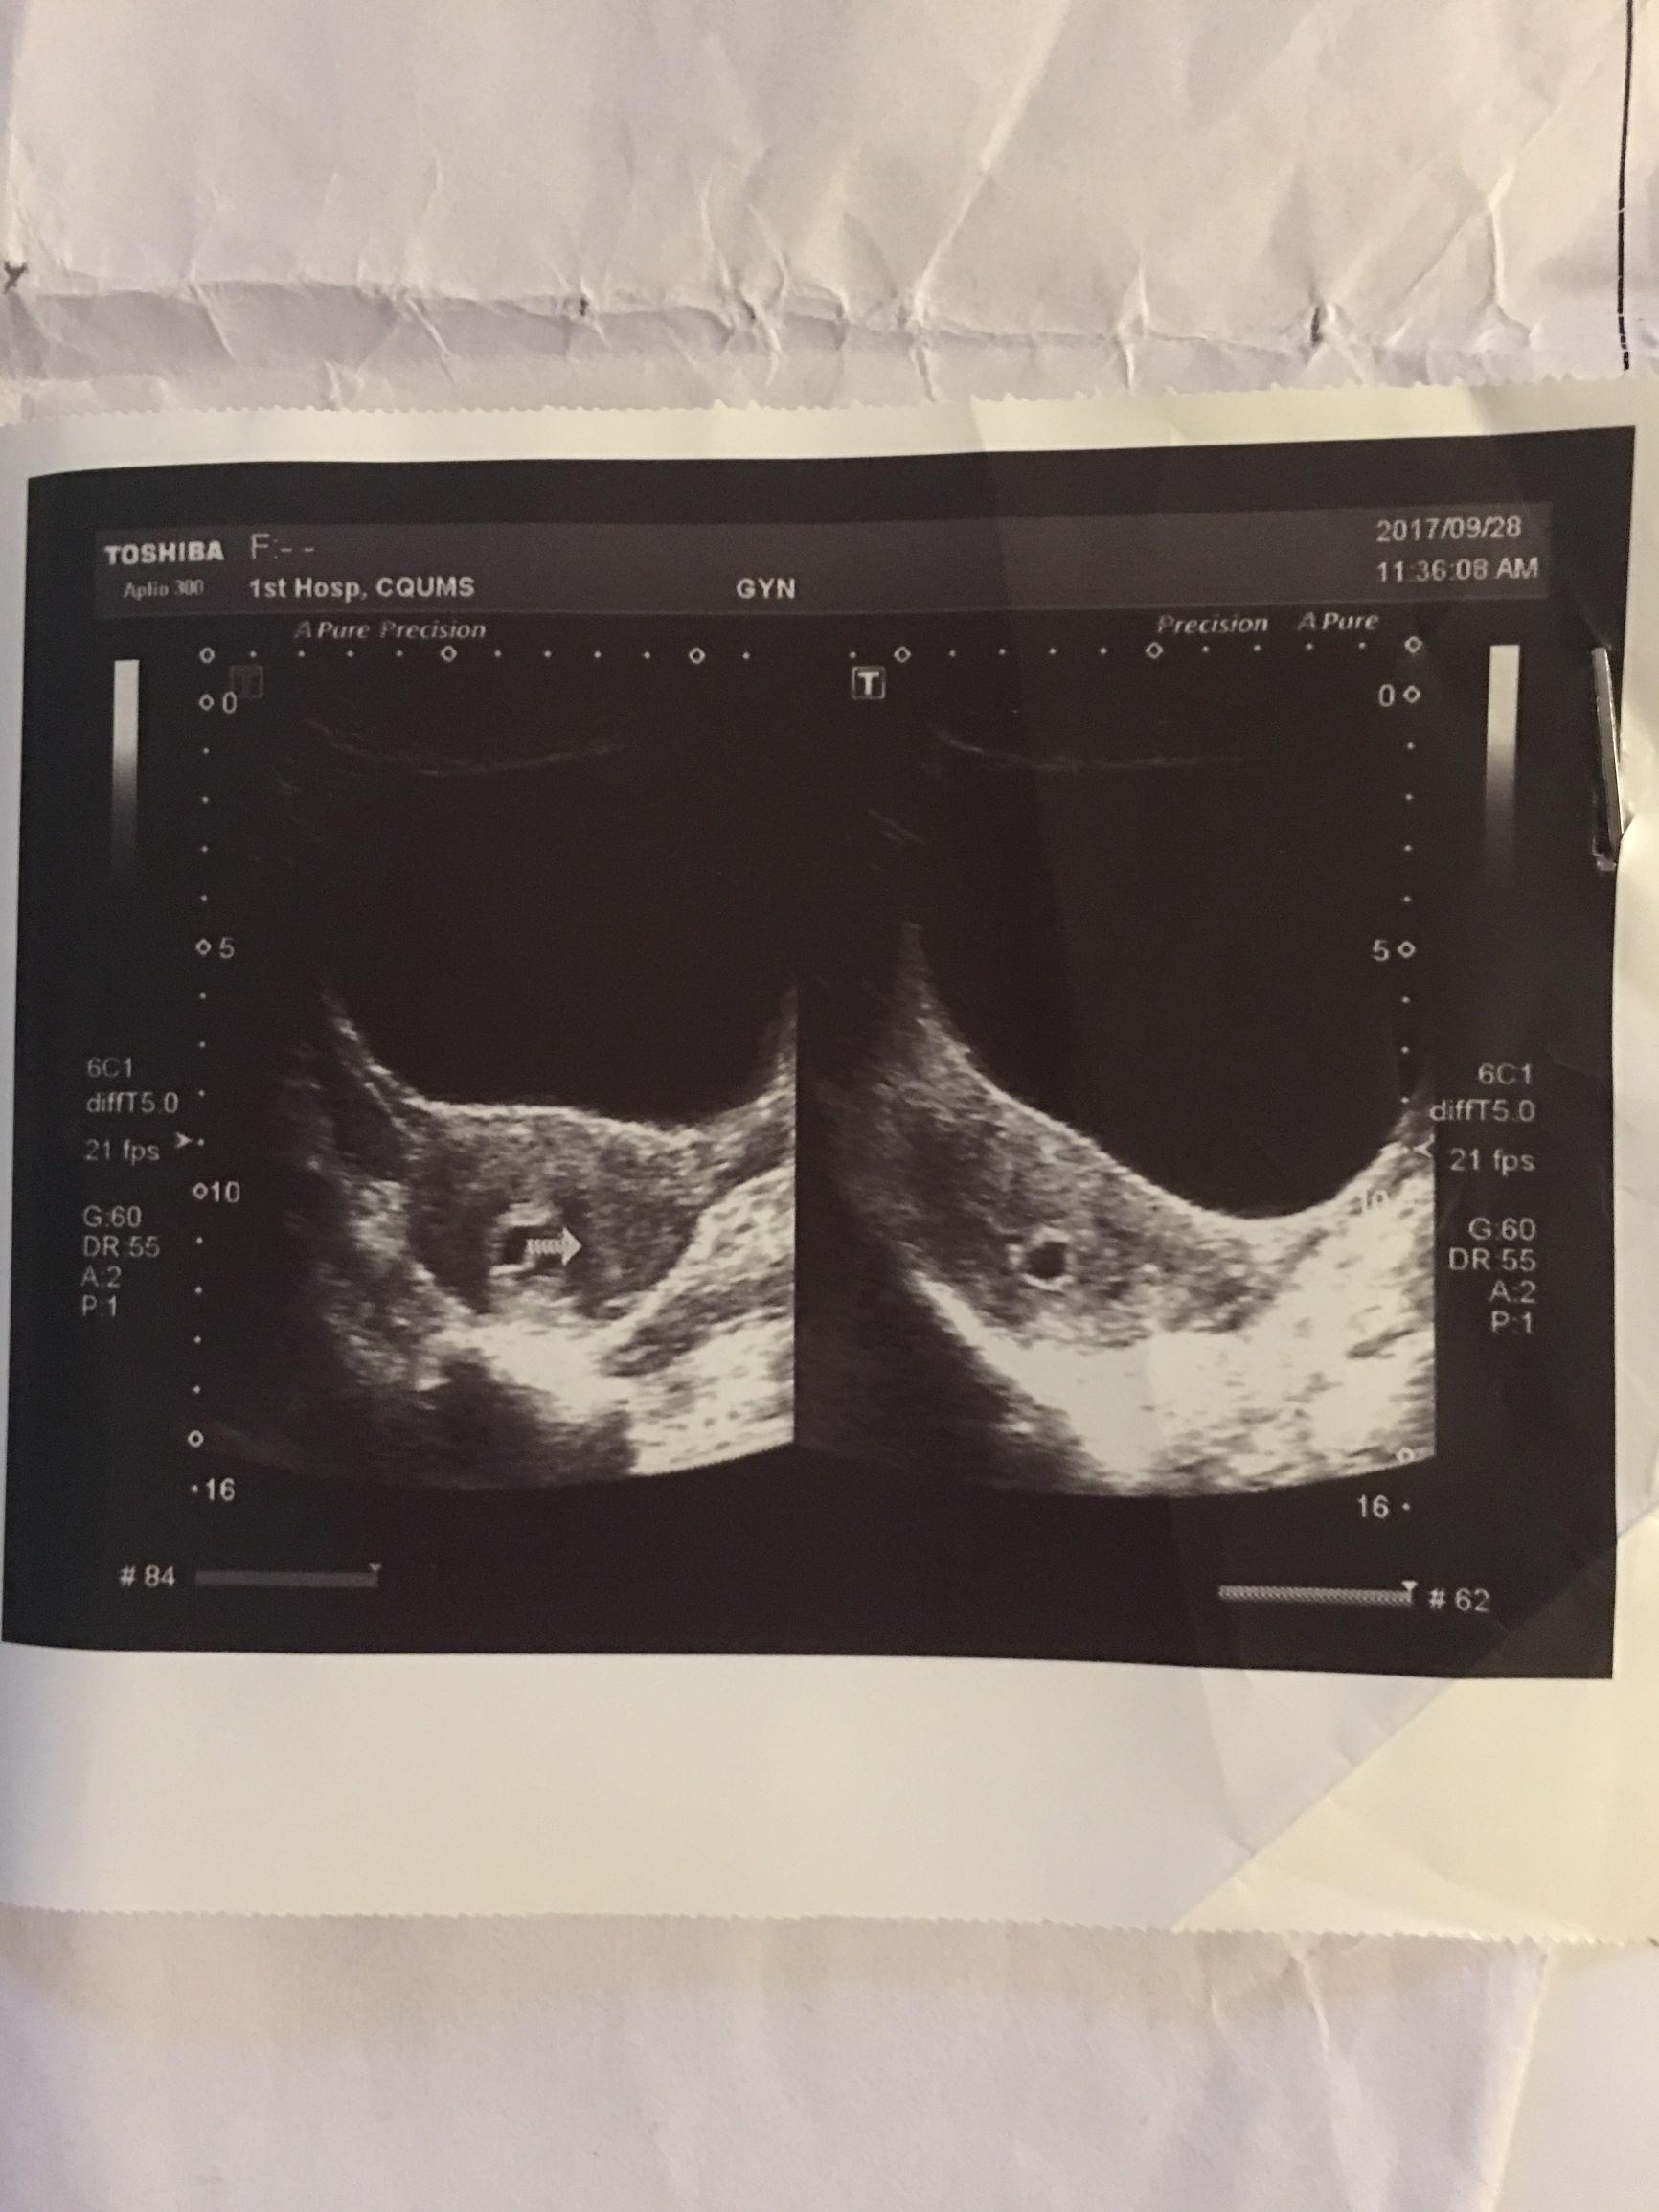

2、復查B超:藥流后一周,建議女性進行B超檢查,以了解子宮內(nèi)是否有殘留物。